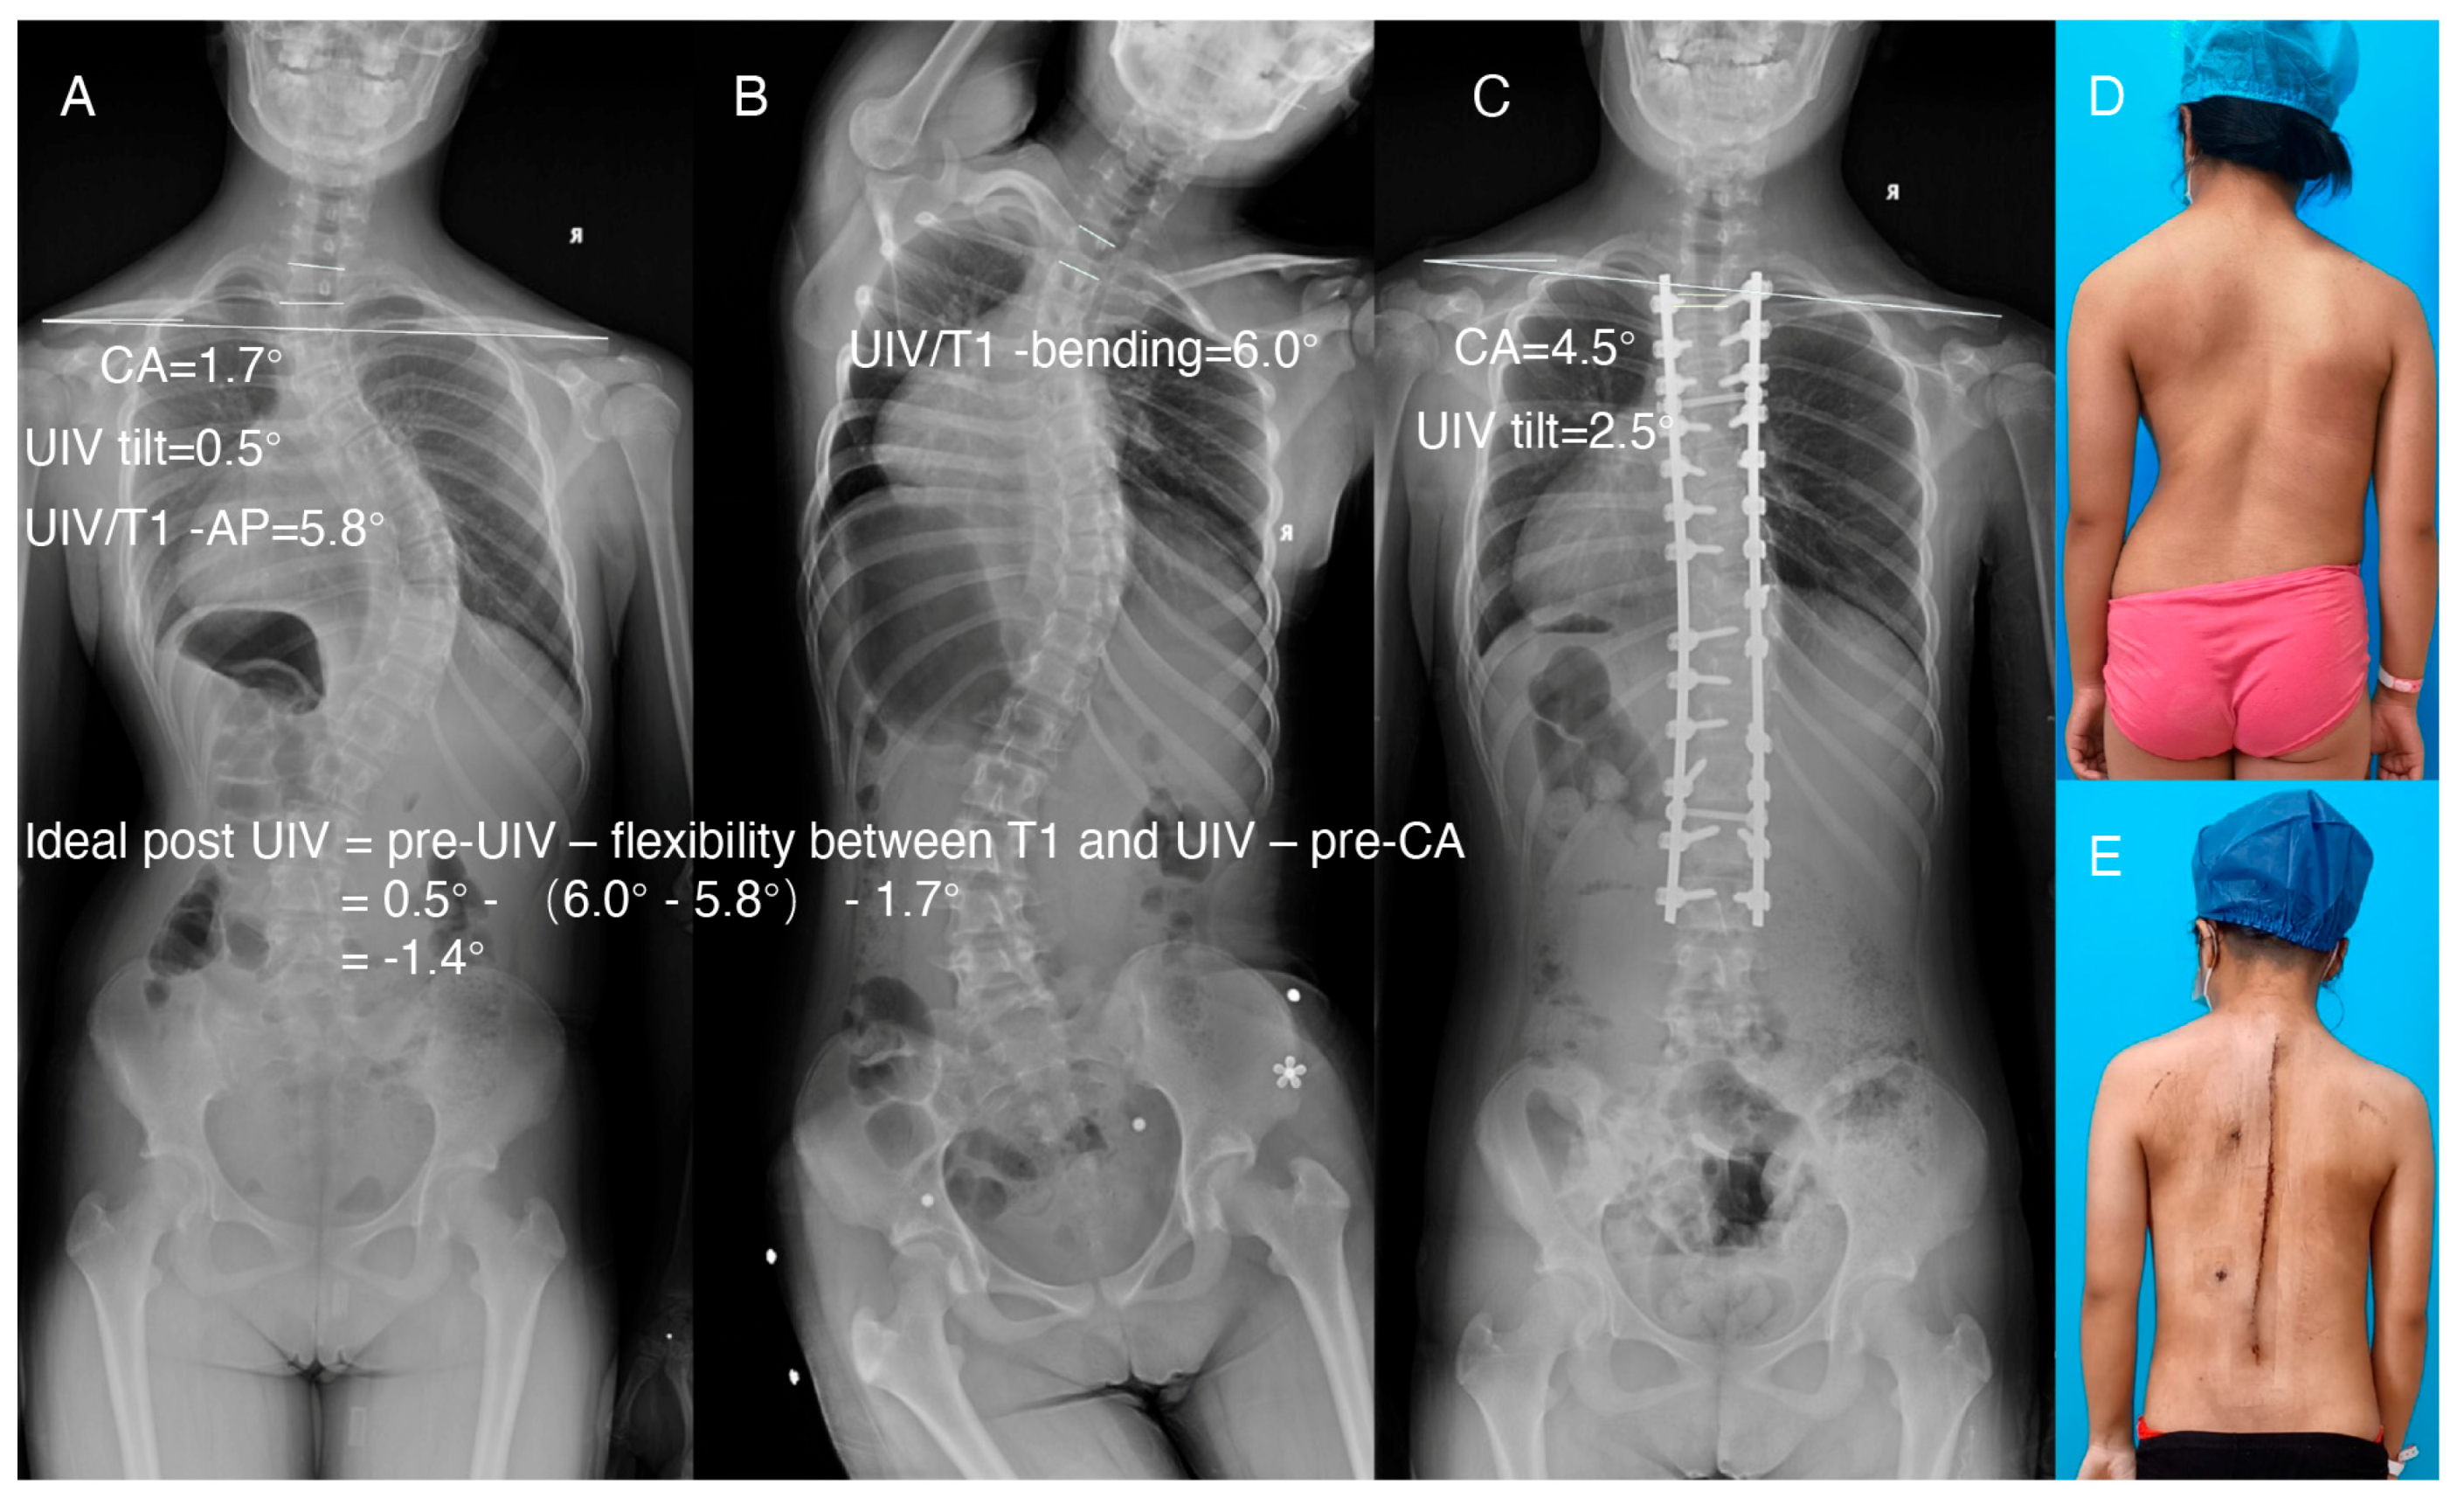

2.4. Verification of the Feasibility of This Method in Clinical Practice